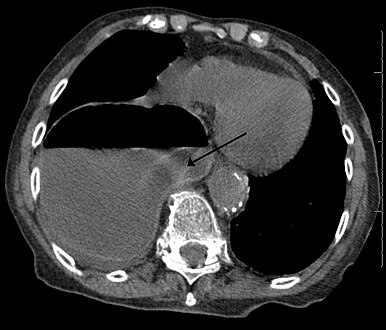

In most cases, postnatal diagnosis is done and up to 2011, only four cases are reported via prenatal diagnosis.[3] Congenital diaphragmatic hernia and intrauterine growth retardation (these two signs put the patients at the risk of afflicting with ring chromosome 15) by fetal ultrasound (Obstetric ultrasonography) at the time period of 16–24 weeks, further investigation and diagnostics (such as karyotyping) must be performed to test the possibility of ring chromosome 15.[citation needed]

Ultrasound finding in a fetus showing liver herniation into the thorax

Congenital diaphragmatic hernia